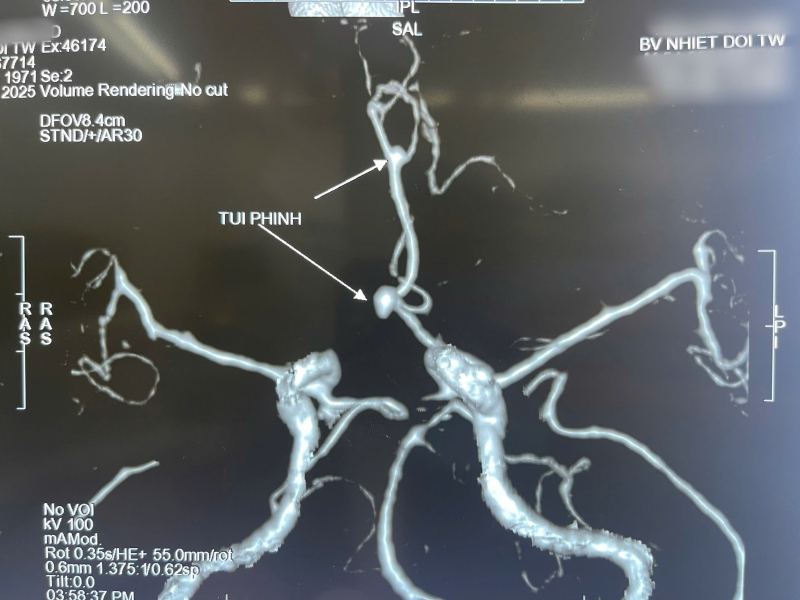

Tại Bệnh viện Bệnh Nhiệt đới Trung ương, kết quả chụp CT não khẩn cấp cho thấy ông C có xuất huyết dưới nhện lan tỏa hai bên - dấu hiệu điển hình của vỡ phình động mạch não. Kết quả chụp phim dựng hình mạch máu não xác định người bệnh có hai túi phình, trong đó túi phình động mạch thông trước đã vỡ, túi phình còn lại ở não trước kích thước nhỏ.